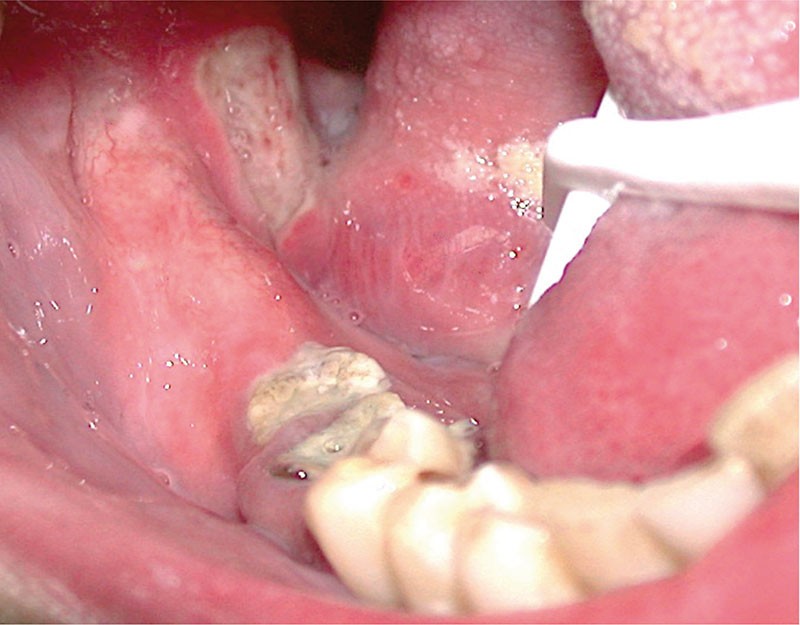

Les aphtes bucco-pharyngés sont des ulcérations spécifiques siégeant le plus souvent sur la muqueuse non kératinisée. On distingue les aphtes miliaires, géants et vulgaires. Les aphtes doivent être différenciés des ulcérations aphtoïdes qui sont secondaires à une cause générale le plus souvent. Les aphtes et les lésions aphtoïdes récidivantes doivent faire rechercher une cause générale et une maladie de Behcet. Le traitement des aphtes repose en première intention sur la corticothérapie locale et la prévention des récurrences sur un traitement par colchicine au long cours.

DÉFINITION

Les aphtes sont des ulcérations de la muqueuse buccale spécifiques, secondaires à une vasculite leucocytoclasique. Les aphtes buccaux sont sporadiques ou récurrents dans l’Aphtose Bucco-Pharingée Récidivante (ABPR). La forme clinique la plus sévère de l’ABPR est la grande aphtose de Touraine plus connue sous le nom de maladie de Behcet.